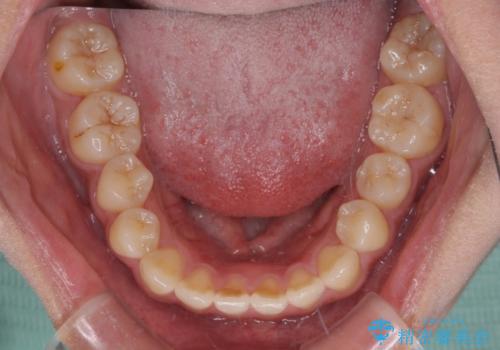

- 前歯の開咬と、上顎前歯の八重歯やデコボコを気にして来院された患者様です。

上顎骨を拡大することで、八重歯やデコボコを歯列に収めることができ、下顎の歯が外に位置していた奥歯の咬み合わせも改善することができました。